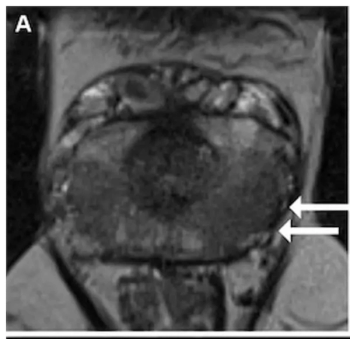

Study: MRI-Based AI Enhances Detection of Seminal Vesicle Invasion in Prostate Cancer